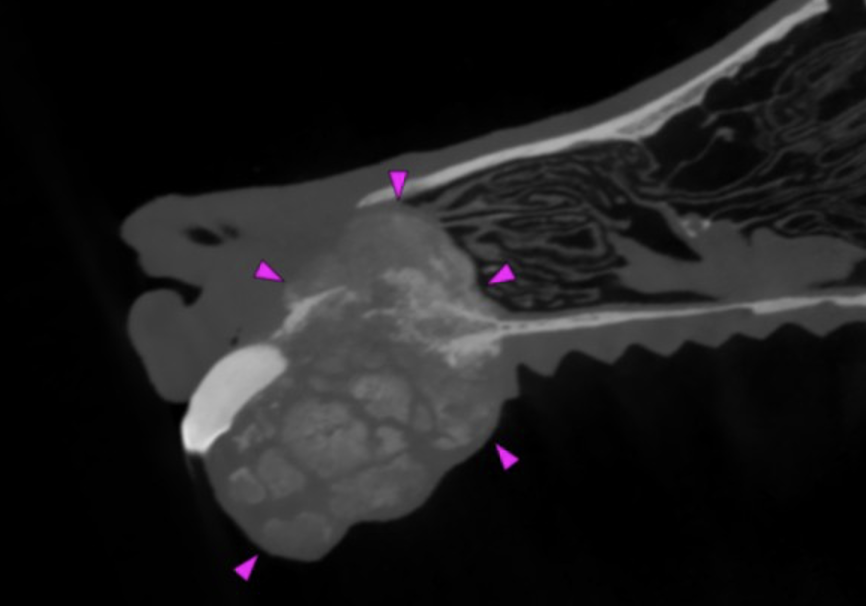

Wegen der klinisch sichtbaren Progression erfolgte die erneute Vorstellung zur weiterführenden Bildgebung. Die durchgeführte CBCT-Untersuchung zeigte eine große, heterogene, überwiegend osteoproduktive Masse des vorderen Oberkiefers. Der Tumor infiltrierte die linke Nasenhöhle, überschritt die Mittellinie und führte zu ausgeprägten knöchernen Destruktionen mit Verlagerung der Schneidezähne. Hinweise auf eine pulmonale Metastasierung ergaben sich in der Thoraxdiagnostik nicht. Das präoperative klinische Staging wurde als Stadium III (T3b, N0, M0) eingestuft. Trotz der ungünstigen Befundlage wurde nach ausführlicher Aufklärung der Besitzer eine operative Therapie angestrebt.